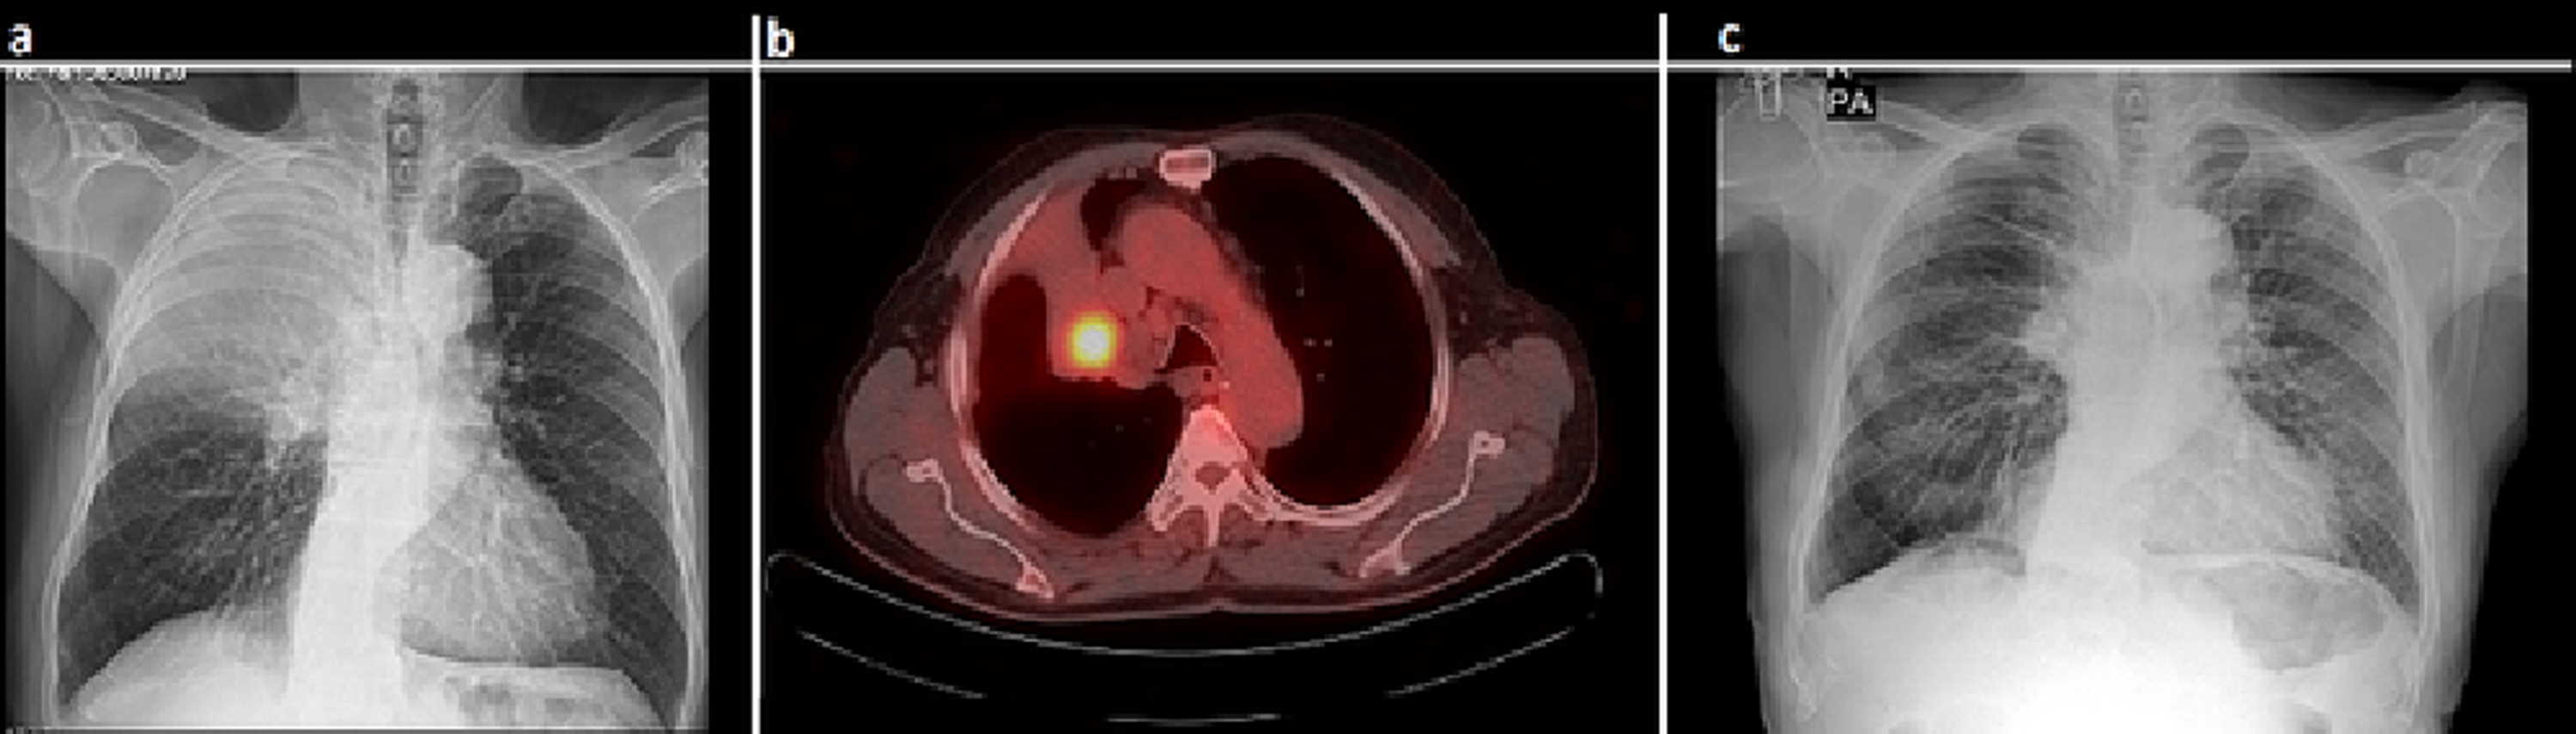

From www.cureus.com

Cureus Videothoracoscopic Bronchial Sleeve Resection for NonSmall What Is A Sleeve Resection Lung The entire lung is removed. Segmental resection a small portion of the lung is removed following anatomical lines. Pulmonary sleeve resection is a type of complex lung resection and reconstruction surgery typically performed for patients with locally advanced lung cancer that involves. A lobe of the lung is removed. Pulmonary sleeve resection (psr) is a broad term to describe circumferential. What Is A Sleeve Resection Lung.

From www.clinicalradiologyonline.net

Postoperative complications of pulmonary resection Clinical Radiology What Is A Sleeve Resection Lung Pulmonary sleeve resection is a type of complex lung resection and reconstruction surgery typically performed for patients with locally advanced lung cancer that involves. Segmental resection a small portion of the lung is removed following anatomical lines. In sleeve resection either one third or one half of a lung is removed, along with lymph glands around it. Standard sleeve resection. What Is A Sleeve Resection Lung.